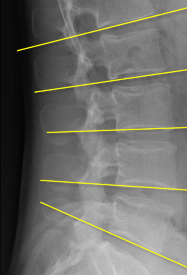

Q what is the name of this measurement? and what is the average + range?

A: Lumbar Lordosis

assesses the curvature of the lumbar spine. The normal range is 50-60°.